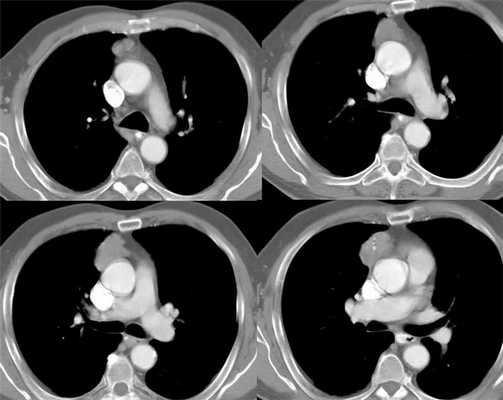

При проведении компьютерной томографии оценивают наличие вилочковой железы и положение в средостении: уровень и отношение к срединной линии, ее форму, линейные размеры, однородность структуры, четкость контуров, измеряют плотность нативно, а также в артериальную, венозную и отсроченную стадии. Аксиальные изображения КТ и комбинированные мультиплоскостные реконструкции могут быть использованы, чтобы идентифицировать инвазию опухоли в крупные кровеносные сосуды, перикард и легочную ткань. Если, опухоль имеет гладкие, четкие границы, однородную плотность, отсутствуют некрозы или кистозные изменения, видна жировая прослойка между опухолью и смежными структурами новообразование можно считать неинвазивным. Если, опухолевое новообразование имеет дольчатую или неправильную форму, нечеткие контуры, неоднородное усиление после внутривенного контрастирования, явное прорастание перикарда, легочной ткани, грудной стенки такую опухоль необходимо считать инвазивной.

Дифференциальная диагностика между гиперплазией и тимомой (рис.3-7) небольших размеров заключается в выявлении новообразования, локально выходящего за контур железы накапливающего контрастное вещество в разные фазы контрастирования отлично от неопухолевой ткани вилочковой железы.